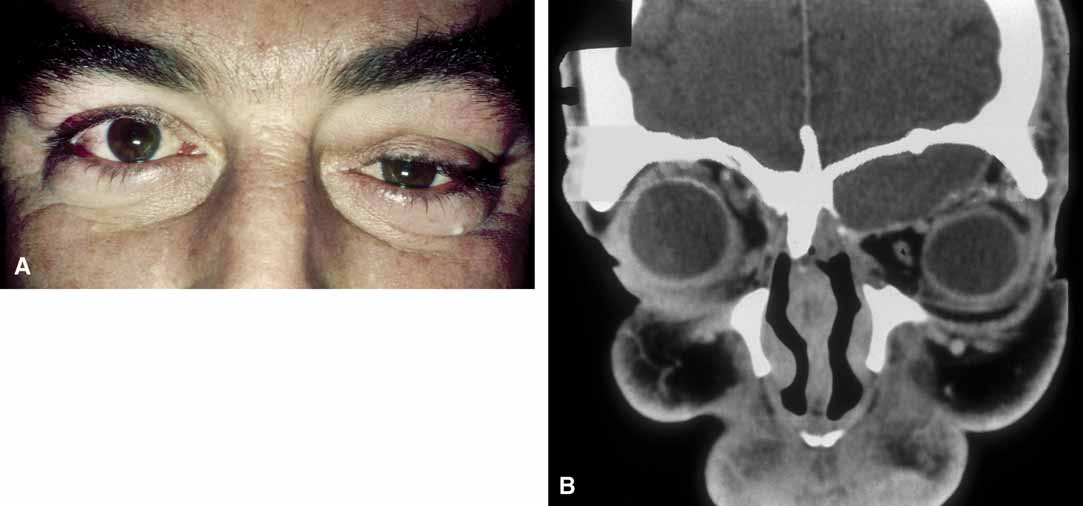

Hematic cysts are uncommon, and the clinical history and ophthalmic findings rarely are diagnostic.48–50 Mass effect with proptosis, globe displacement, and motility disturbance are common with chronic hematic cysts. Spontaneous eyelid ecchymosis and edema may suggest this diagnosis (Fig. 10). In acute hematic cysts, optic nerve signs may be present, including decreased vision, afferent pupillary defect, and choroidal folds.51

Fig. 10 A. Spontaneous periorbital ecchymosis and diplopia in a man who had undergone a left orbital blowout fracture 5 years previously suggest the presence of a hematic cyst. B. Computed tomogram shows the left globe and a previously placed Silastic plate displaced superiorly by the expanding hematic cyst in the floor of the left orbit.